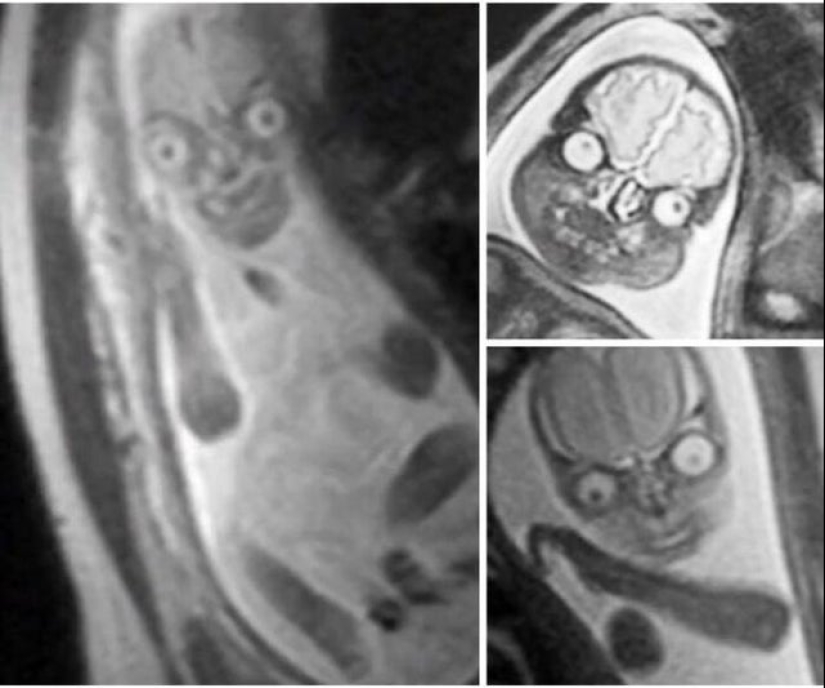

Resonancia magnética del bebé durante el embarazo.